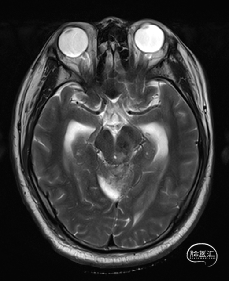

术前MRI检查

术前MRI检查提示左侧丘脑中脑海绵状血管瘤并卒中,梗阻性脑积水;

根据MRI及DTI显示,只有在丘脑与上丘之间的点(dot)进入病变才可能在切除病变时最大程度保护神经功能,由于上述原因,该“点”在术中显露极其困难,虽有导航指引,电生理监测的条件下,对术者的耐心、技术、经验及体能依然是极大的挑战;

本例患者磁共振检查清晰显示病变位于左侧丘脑中脑区域,且位于丘脑内下方向中脑顶盖延续,病变的上部、前部、外侧部都有重要的神经组织,因此,手术从上方、前方、外侧方向切除病变均难以实施;

术前详细的磁共振检查,包括平扫增强,SWI及DTI,可以规划出手术最适宜的路径及切入点;